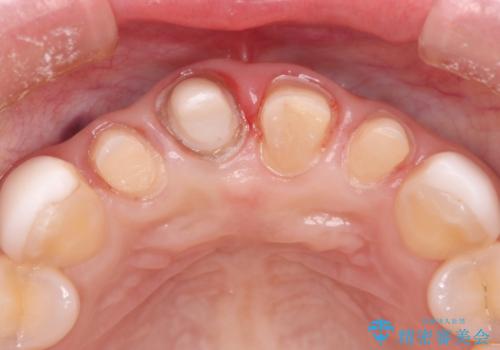

- 他院で治療した前歯の色が気になるということで来院された患者様です。前歯に色の差があり、レントゲンから内部にう蝕も見られたため、審美性に優れ、う蝕になりにくいオールセラミッククラウンで治療いたしました。

清掃性も上がったおかげで、歯肉の状態も良好に保てています。

色の調和もとれたので非常に満足いただけました。